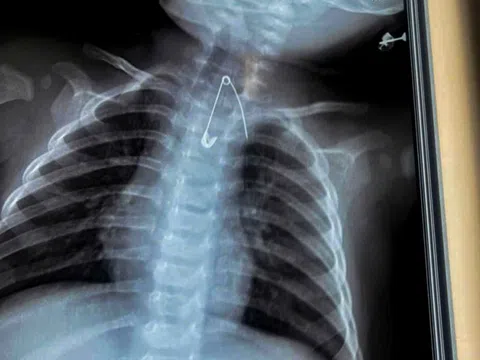

Bé trai 3 tuổi dùng gậy đánh vào chó nhà nuôi, chó cắn thấu ngực, tràn máu

Bé trai, 3 tuổi, ở Hải Phòng bị chó nuôi trong gia đình cắn, gây ra vết thương thấu ngực và tràn máu, tràn...